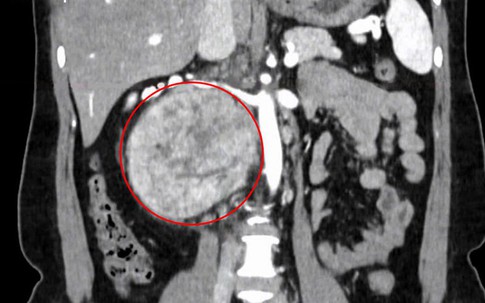

GĐXH - Khối u rất lớn, kích thước 12 cm nằm sau tĩnh mạch chủ, cạnh động mạch và hai tĩnh mạch thận, gây chèn ép... khiến người bệnh bị đau lưng âm ỉ.